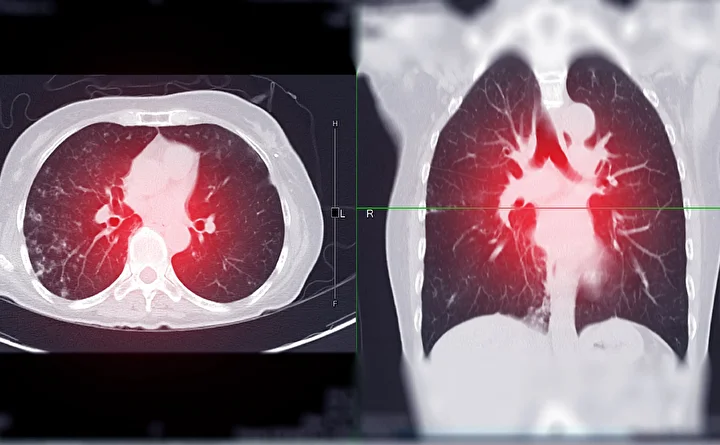

Akciğer kanseri genellikle öksürük, nefes darlığı, göğüs ağrısı ve kilo kaybı ile kendini gösteriyor, ancak erken evrede fark edilmesi güç. 50-80 yaş arası, 20 paket-yıl sigara öyküsü olan bireyler için düşük doz bilgisayarlı tomografi (BT) taraması hayati önem taşıyor. Erken tanı konulan hastalarda sağkalım oranı yüzde 60-90’a kadar çıkabiliyor.